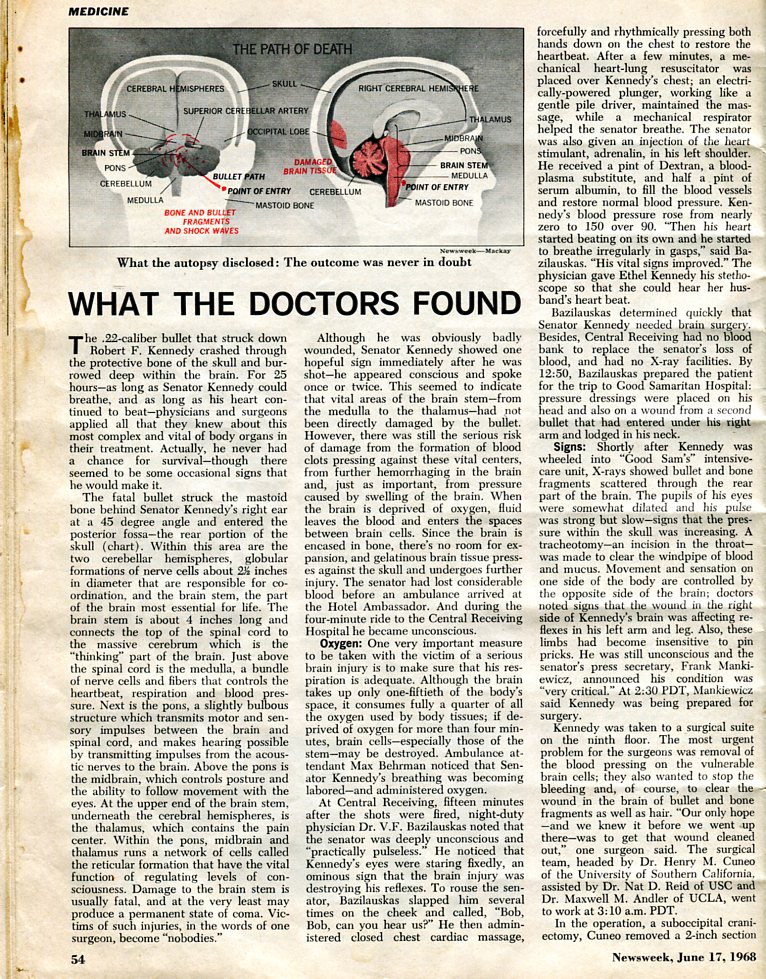

RFK shot-behind-ear by security guard says RFKjr

BOBBY GRABBED KILLER'S TIE

& BULLET BEHIND EAR KILLED RFK

& RFK PHOTO PROVES BULLET BEHIND

& RFK ASSASSINATION PUZZLE PIECES